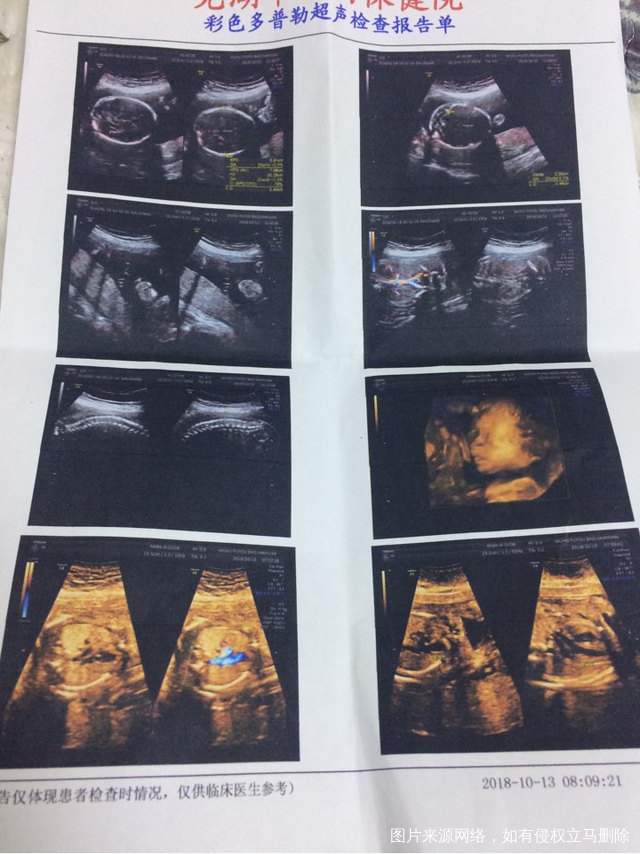

你好,三维显示左心室内见一枚强光点这个对宝宝有影响吗?

医生麻烦帮忙看看报告是否正常有地中海贫血吗